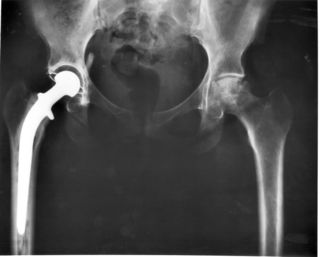

صورة بأشعة إكس، مفصل المريض (يسار الصورة) تم استبداله، with the ball of this ball-and-socket joint replaced by a metal head that is set in the thighbone or femur and the socket replaced by a white plastic cup (clear in this X-ray). Pelvic anatomy consistent with that of a female (large infrapubic angle, large pelvic opening).